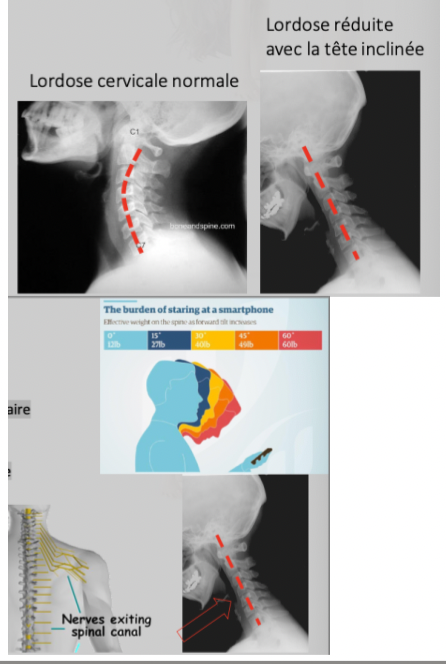

Walking & tEXTING or TextNeck

Posture caractérisée

- Tête penchée

- Cou allongé

- Épaules arrondies

- Dos courbé

- Perte de la lordose cervicale

Conséquences

* Étirement/tension muscu

* Nerf coincé

* Hernie discale

* Dégénérescence du disque

* Maux de tête

* Douleur au cou